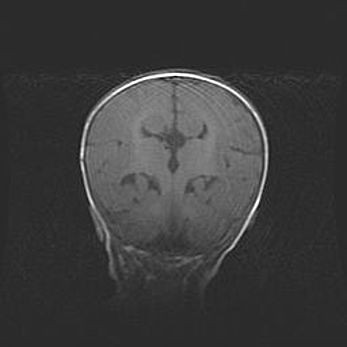

Открытая гидроцефалия.

Возраст: 6 месяцев 15 дней

Вес: 6200 г

Пол: женский

Окружность головы: 41 см

Срок гестации: 38 недель

Гидроцефалия головного мозга у новорожденных – это скопление избыточного количества цереброспинальной жидкости в головном мозге. Ее избыточное скопление в мозге приводит к патологическому расширению желудочков мозга (четырех полостей, расположенных в глубине белого вещества мозга, заполненных цереброспинальной жидкостью и связанных узкими проходами).

Открытый тип гидроцефалии (сообщающаяся) наблюдается тогда, когда нарушен механизм всасывания ликвора в системный кровоток. При этом типе причиной заболевания чаще всего является перенесенные ранее инфекции (например: менингит),  либо же наличие крови в субарахноидальном пространстве.